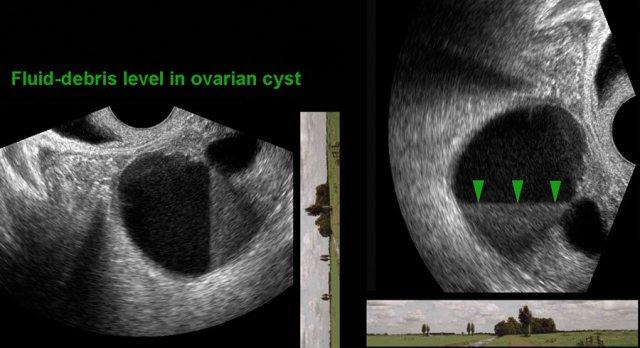

Điều này không nhất thiết là vấn đề, miễn là người đọc nhận thức được sự khác biệt trong cách trình bày giải phẫu, bao gồm cả ảnh hưởng của trọng lực.

Lưu ý đường chân trời trong tương quan với hình ảnh TVUS.

Chẳng hạn, ở bệnh nhân này có nang lạc nội mạc tử cung, mức dịch-cặn lắng nằm theo hướng thẳng đứng và do đó có thể bị diễn giải sai.

Vấn đề này có thể được khắc phục bằng cách xoay hình ảnh siêu âm 90 độ theo chiều kim đồng hồ (hình bên phải).

Tuy nhiên, việc tùy tiện thay đổi hướng hình ảnh siêu âm sẽ không có lợi cho việc nhận dạng hình ảnh theo mẫu. Vì lý do này, tốt nhất nên duy trì một hướng nhất quán.